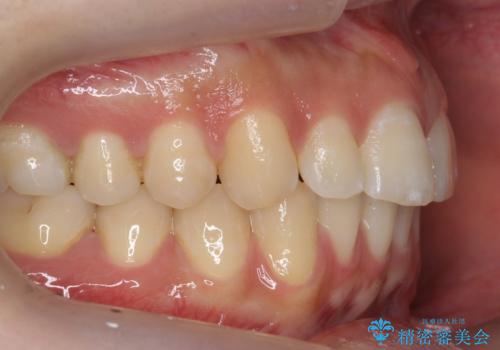

- 上下の歯のすき間を気にして来院。

当初はセラミックでかぶせて上だけ治そうかな、というご希望でした。

患者様の歯は咬耗といって削れて短くなっていたため、セラミックでかぶせると隙間をうめるため横長の歯になりそうでした。術後の見た目は矯正の方が自然にみえるとお伝えしました。

また、歯ぎしりがありそうなので、セラミックにしたときにセラミックが欠けてしまうリスクもありました。

時間はかかるが矯正治療で天然の歯の隙間をつめて歯を削らなくて済むというご案内をしたところ、セラミックでかぶせるのはやめて、矯正治療を行うことになりました。

それぞれ特徴がありますので十分お考えの上選んでいただき、治療結果には満足していただけたと思います。